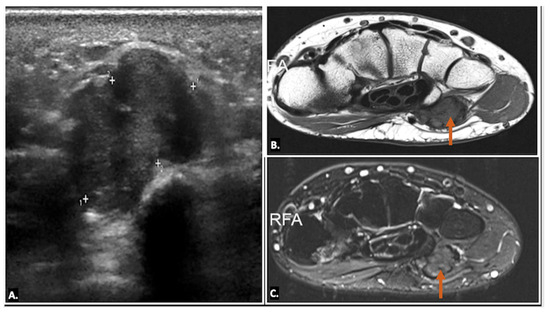

On plain radiographs, calcific tendinopathy is typically seen as well-defined, amorphous, or cloud-like calcifications along the course of the flexor carpi ulnaris tendon near the pisiform bone. On ultrasound imaging, calcific deposits within the tendon appear as hyperechoic foci with posterior acoustic shadowing. These deposits are typically well-delineated in chronic cases. In acute calcific tendinitis, surrounding soft tissues may show signs of decreased echogenicity, indicating oedema and inflammation, and there may be associated fluid. Doppler ultrasound often shows increased vascularity surrounding the inflamed tendon and calcium deposits, consistent with acute inflammation (Figure 13) (Video S2). A synovial bursa is situated between the tendon and the pisiform bone. In some cases, patients may develop calcific bursitis. Ultrasound imaging is highly sensitive in detecting calcific deposits and assessing surrounding soft-tissue involvement, such as ulnar nerve inflammation or compression. Ultrasound imaging allows for dynamic assessment and is particularly useful in real-time evaluation and guidance for interventions such as aspiration [21,22].

Figure 13.

(A) Plain radiograph showing a radio-dense lesion located anterior to the pisiform bone. (B,C) Gray-scale Axial Ultrasound images of the same patient showing hyperechoic foci (orange arrow) at the flexor carpi ulnaris insertion over the pisiform bone, in keeping with flexor carpi ulnaris (FCU) calcific tendinopathy. (C) Gray-scale Longitudinal Ultrasound image showing calcium extending into the adjacent soft tissue. Ultrasound image with colour Doppler overlay demonstrates increased vascularity within the flexor carpi ulnaris (FCU) tendon and surrounding soft tissues, suggesting active inflammation.